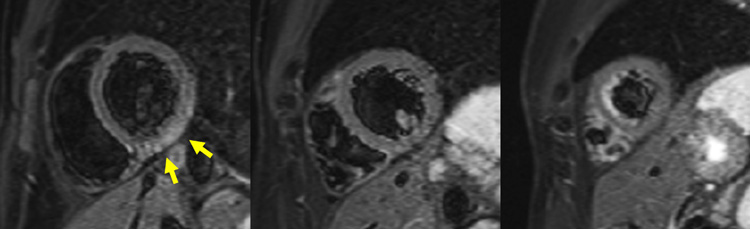

Figure 3A : Séquence T2 STIR - Coupes petit-axe

Figure 3B : Séquence T2 STIR - Coupes long-axe

Figure 6A : Séquence T2 STIR - Coupes petit-axe

Figure 6B : Séquence T2 STIR - Coupes long-axe

Présence d’une zone d’œdème myocardique inféro-latéro-basale et inféro-basale avec un hyper-signal T2 (zones blanches, flèches jaunes), comparé au reste du myocarde en iso-signal (le reste du myocarde est gris).

Astuce quant à l'analyse du T2-STIR

- La séquence de T2-STIR inclut une préparation de l’aimantation qui permet d’annuler le gras et le sang. Ainsi, on peut retenir que la seule entité qui est théoriquement censée être en hypersignal est l’œdème myocardique.

- Cependant, veuillez noter ici qu’une partie du sang n’a pas correctement été annulée au niveau des apex du VG et du VD. Il s’agit d’un artéfact classique sur ce type de séquence, qui correspond à des globules rouges moins en mouvement au niveau de l’apex, et qui sont donc moins bien annulés.

- Enfin, retenez que le principal avantage de la séquence de T2-STIR par rapport au T2 mapping est de pouvoir visualiser un éventuel œdème au niveau du péricarde ! Cependant, ici, malgré la douleur d’allure péricarditique cliniquement, on ne note pas d’hypersignal du péricarde. En effet, la sensibilité de l’IRM cardiaque n’est pas de 100 % pour le diagnostic de péricardite aiguë !